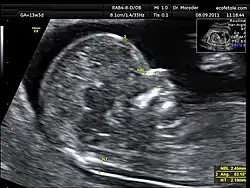

Ultrassom demonstrando a translucência nucal em feto de 13 semanas.

Uma das grandes contribuições da pesquisa ultra-sonográfica do final do século 20 foi a demonstração de que o acúmulo excessivo de fluido na nuca do feto, conhecido como translucência nucal (TN), está correlacionado com anomalias cromossômicas, malformações fetais e síndromes genéticas.